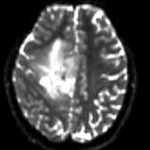

This is a classic case of a multi-sequence MRI exam we wish to spatially align to the anatomical reference scan (T1-SPGR). The scan of interest is the DTI image to be aligned for surgical planning/reference. The key points are: 1) the DWI sequence (EPI) contains distortions we seek to correct via non-rigid alignment; 2) the DTI baseline is similar in contrast to a T2, albeit at much lower resolution, but we do not have a T2 weighted anatomical scan, but instead a T1 and a FLAIR. So we use the FLAIR as the fixed image, because its contrast matches the DTI-baseline better than the T1, esp. in terms of tumor contrast.

• the DTI-FLAIR registration includes non-rigid deformation to correct for the strong distortions from the EPI acquisition. Because of the nonrigid component a mask of the brain parenchyma helps in obtaining a meaningful transform. Registration without a mask is possible but not as good as with a mask.

RegLib C27 Result1.gif original and registered pair of FLAIR and DTI (click to enlarge)

RegLib C27 Result2.gif original and registered pair of T1 and DTI (click to enlarge)